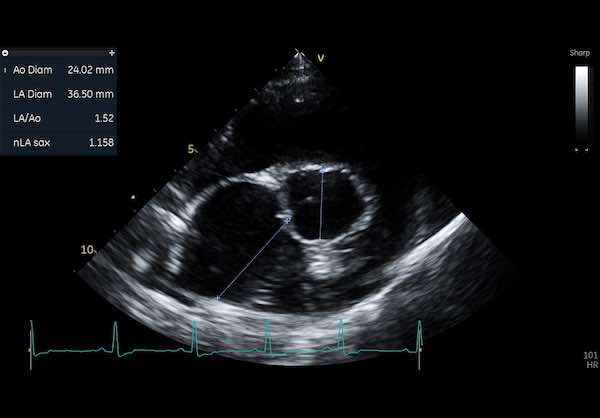

🩺 Echocardiogram (ECG): This is an ultrasound of the heart and is one of the best ways to see how well your dog’s heart is functioning.

An echocardiogram is typically the most informative test and provides detailed images of the heart’s structure and function.

While on an echocardiogram you can measure all the internal chamber sizes to fractions of a millimetre.